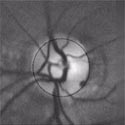

Here are retina images from twins / Ci-dessous deux rétines de jumeaux:

A kind of (circular) barcode is extracted from the pattern of blood vessels, which is stored for further comparison with a new retina image.

First the intensity profile is extracted, then a circular scan is performed to locate blood vessels.